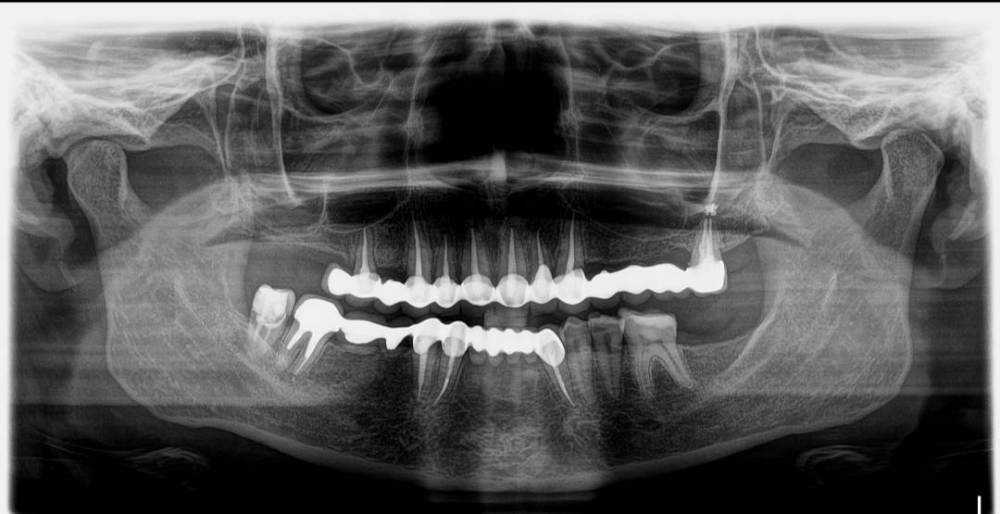

Ekaterina 03 Опубликовано 16 июня, 2021 Поделиться Опубликовано 16 июня, 2021 (изменено) Доброго времени суток . Снимок февраль 2021. Обострение пародонтита. После лечения снова рецидив на данном этапе времени. Идёт воспалительный процесс справа. Хочу снять мост, Возможна ли имплантация при пародонтите? Так же хотелось бы узнать примерную стоимость верхней челюсти "под ключ" по протоколу все на 4-х г. Москва Изменено 16 июня, 2021 пользователем Ekaterina 03 Ссылка на комментарий

Ekaterina 03 Опубликовано 17 июня, 2021 Автор Поделиться Опубликовано 17 июня, 2021 А что можно сделать в данной ситуации? Три зуба справа пародонтит. Постоянно рецидивирует. Лечение не помогает. Делали кюретаж, убрали камень, лазер. Это уже 2а раза. Последний раз месяц назад. Сейчас опять воспаление . Во рту привкус сукровици,постоянная головная боль и отдаёт в шею. Подскажите, что можно сделать? Новый мост? Этот простоял около 4-х лет. Этой весной научились проблемы, которые не заканчиваются. Ссылка на комментарий